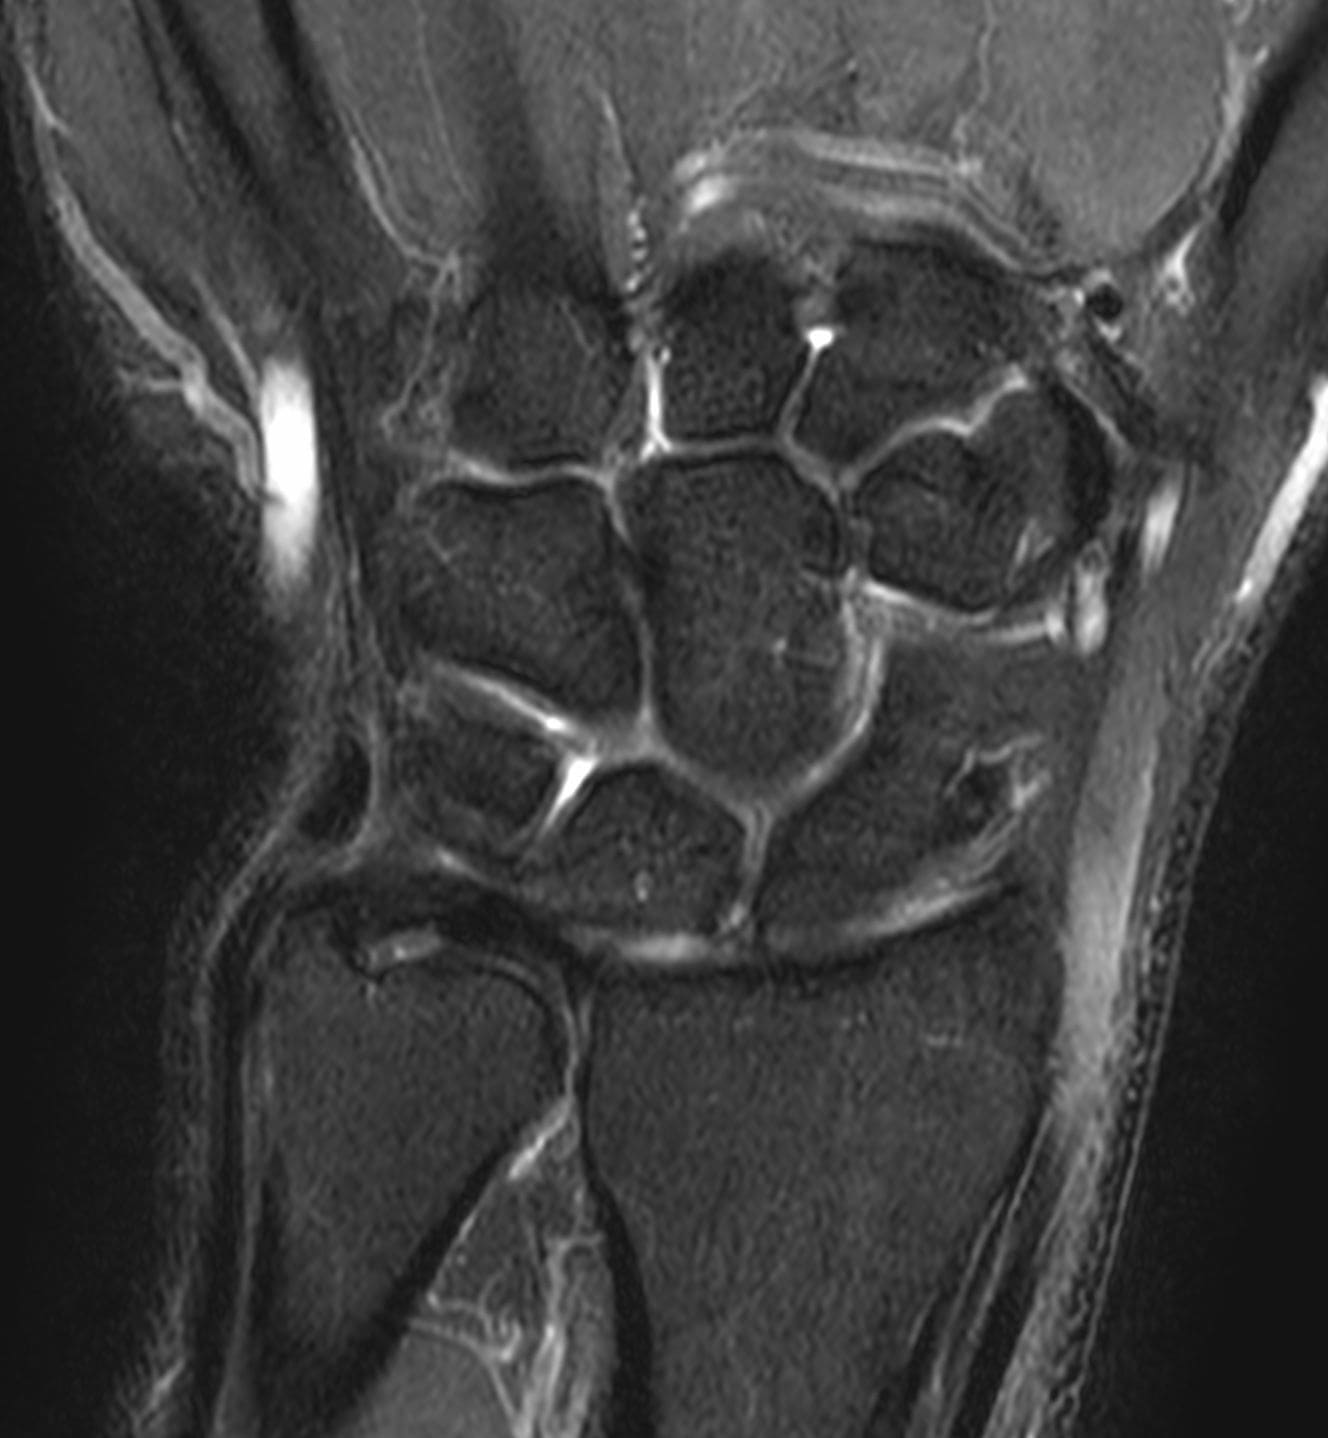

EVAA Radiology provides comprehensive teleradiology services across all subspecialties, with a commitment to excellence and a personal touch—ensuring that referring doctors always have access to a radiologist for discussion whenever needed.

At EVAA Radiology we provide tele-radiology services in the following subspecialties –